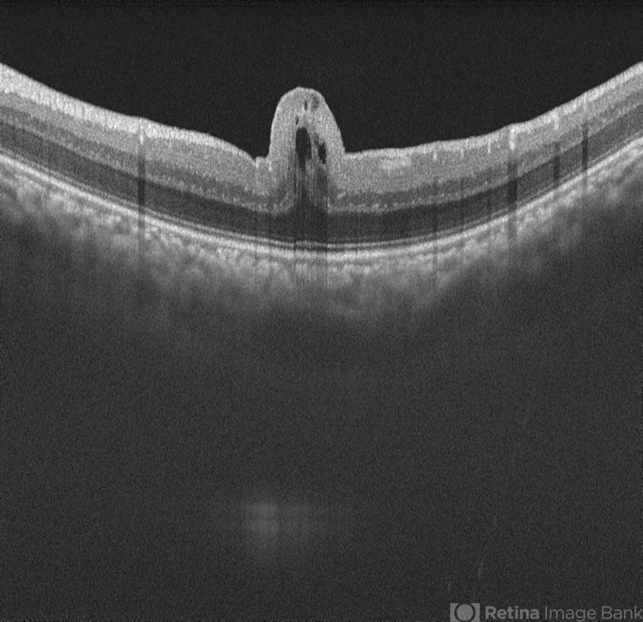

- Swept source OCT image of left eye of 34 year male patient with high hypermetropia(+14). BCVA 20/20 in right eye and 20/60 in left eye. Anterior segment was normal. There is loss of foveal pit with omega shaped elevation of inner retinal layers.